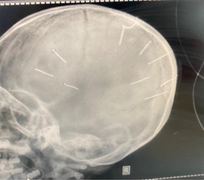

Qua khám nghiệm tử thi bé gái 3 tuổi bị người tình của mẹ bạo hành, cơ quan chức năng tìm thấy 10 chiếc đinh dài khoảng 2cm trong hộp sọ.

Đại diện Bệnh viện Xanh Pôn cho biết bé gái 3 tuổi bị người tình của mẹ găm 9 chiếc đinh vào đầu đã tử vong.

Bé gái 3 tuổi có nhiều đinh trong hộp sọ vẫn đang được điều trị tích cực tại BV Xanh Pôn, còn mẹ của cháu bị Công an huyện Thạch Thất triệu tập để lấy lời khai.